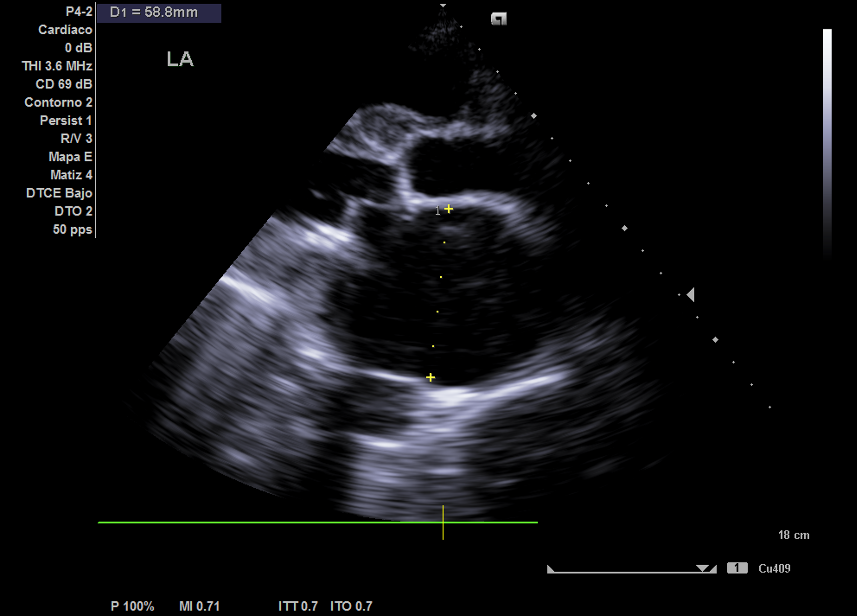

Ecocardiografía: importante dilatación auricular izquierda y derecha, vena cava no colapsable.

El paciente fue citado en cardiología en el plazo de una semana ante las imágenes de la ecografía clínica aportadas, donde se confirmó mediante ecocardiografía: prótesis mecánica mitral disfuncionante por probable trombosis protésica, Insuficiencia tricúspidea muy severa, hipertensión pulmonar severa y datos de congestión venosa sistémica.